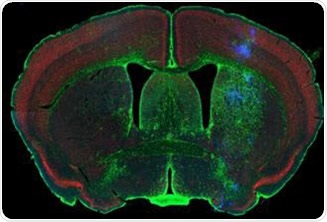

Rodent brain (top) depicting simultaneous acquisition of fluorophores Cy2, Cy3 and Cy5; Brain image (bottom) magnified to 0.5 μm

Figure 1. Rodent brain (top) depicting simultaneous acquisition of fluorophores Cy2, Cy3 and Cy5; Brain image (bottom) magnified to 0.5 μm. Image credit: Huron Digital Pathology.

• This is the only confocal fluorescence digital slide scanner that enables the simultaneous acquisition of up to three fluorophores spanning the whole visible spectrum, from 400nm-850nm. This provides considerable time-savings and less photo bleaching due to the unique flying-spot laser platform.